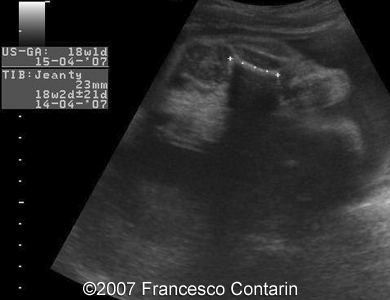

This is a 22-year-old woman (G4, P2) with unremarkable familiar history, referred to our hospital at 29 weeks of gestation due to a fetal ascites. There were no signs of maternal-fetal blood incompatibility. The ultrasound investigation revealed rhizomelia, postaxial polydactyly, small thorax, short ribs, ascites, increased abdominal biometric parameters, polyhydramnios. We supposed two diagnoses: Short rib-polydactyly syndrome versus Jeune syndrome (asphyxiating thoracic dystrophy).

Images 3, 4. 29th week of pregnancy -  shortened tibia (left); and polydactyly of the hand (right).

Images 5, 6. 29th week of pregnancy -  narrow thorax.